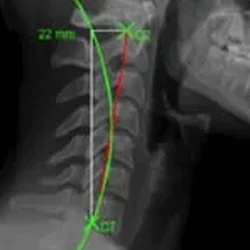

Radiographic Software Mensuration Analysis (RSMA™)

An advanced X-ray analysis tool that uses state-of-the-art radiographic software to detect spinal problems. This tool allows us to detect the severity and location of a patient’s exact root cause of their condition.